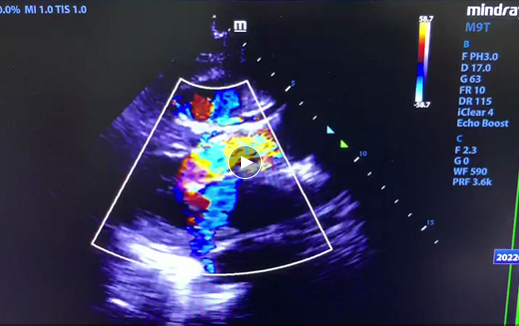

一周前,王女士因胸闷、气促加重,严重影响日常生活,遂就诊于华润武钢总医院心血管内科,接诊的邓建丽主任在给王女士听诊的过程中发现王女士心脏有杂音,细心的邓主任留意到王女士的胸闷、气促症状可能因心脏瓣膜病引起,随即为王女士安排了心脏彩超检查,彩超证实王女士的确存在重度主动脉狭窄合并轻-中度主动脉瓣关闭不全,且主动脉瓣跨瓣压差高达 74 mmHg。高度狭窄的主动脉瓣,导致王女士心脏左心室射血到主动脉的过程受阻,久而久之造成心力衰竭,引起王女士的胸闷、气促症状加重。

术后超声科叶华容主任在手术室为患者进行术后评估,实时超声显示该患者主动脉跨瓣压差由术前的 73 mmHg 直接下降到术后的 16 mmHg,手术效果立竿见影,患者胸闷、气促症状明显缓解,且无传导组织、穿孔等并发症发生,宣告手术圆满结束。